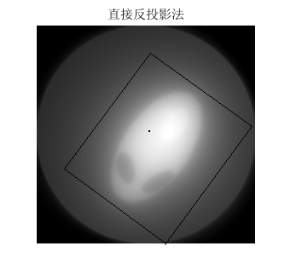

3.算法说明:本文用matlab进行算法实现,由于所给数据一列为一次扫描一列512个数180列,将题中所给的512180接受的数据进行拆分,将一列作为一个投影层。首先,将一列进行复制将第i列变成一个512512的矩阵,该矩阵没一列都是由第i列复制来的,由此可以得到180个矩阵,将第i+1个矩阵旋转1度加到第i个矩阵上,知道加完180个,然后除以射线条数,得到的512512的矩阵为所要成像图形的灰度像素矩阵,然后进行等比例缩小成体重要求的256256大小可得。程序见附录程序三,第一问结果如图九,第二问结果如图十,第三问结果如图十一.

图 9

图 10

图 11

由滤波公式与原来灰度像素矩阵每一列进行卷积,得到了消除边缘失锐的灰度像素矩阵再用原本未滤波的模型进行图形重建运算,程序见附录程序四,结果以及效果如下:

图 14